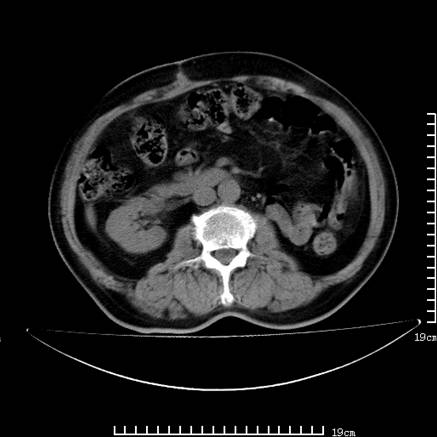

以下是引用lirenxiong在2008-7-19 22:01:00的发言:[br]胆总管结石并胆系感染,胆囊切除术后改变!左肾未见!左肾上腺增生肥大?请全腹扫描,增强!

以下是引用lirenxiong在2008-7-19 22:01:00的发言:[br]胆总管结石并胆系感染,胆囊切除术后改变!左肾未见!左肾上腺增生肥大?增强!